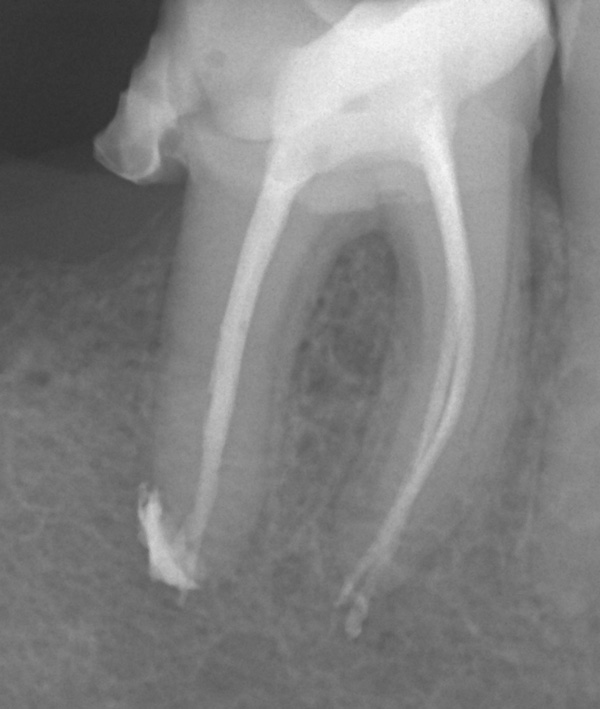

Hier sieht man die Röntgenbilder der Füllungen des Wurzelkanalsystems an den Zähnen 37 und 46:

37: